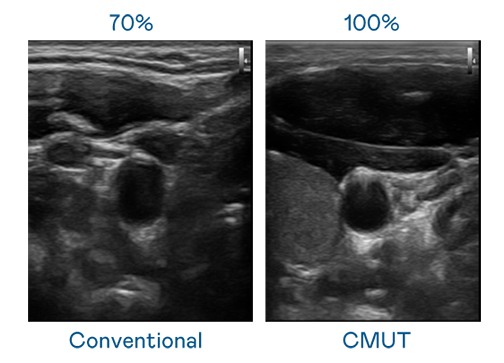

CMUT 技术是一种用电容式微机电元件来产生超音波讯号的技术。与传统 PZT 压电式技术相比,CMUT 频宽增加 30%,更宽频的超音波讯号让影像解析度大幅提升,是实现高影像品质医疗超音波扫描、促进精准医疗发展的关键技术。

超音波影像的解析度高低,首先取决于探头能发出的讯号频宽。至尊国际 CMUT 可提供高清晰的超音波讯号,提供高频宽、高灵敏度、影像纹理细节更高的超音波影像,协助医护人员缩短影像判读时间及利用精准的医疗影像进行诊断。